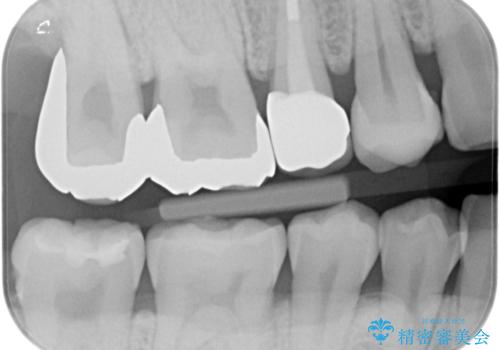

- セラミック治療希望の患者様です。

古い樹脂の材料をとりe-maxの詰め物で治療を行いました。

適合の良い詰め物が入りました。